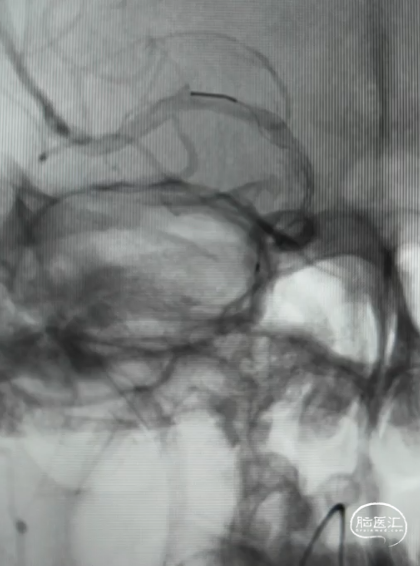

DSA造影(2024.11.07)

右侧颈内动脉起始段闭塞,动脉晚期可见颈动脉颅内段浅淡显影。

前交通动脉开放,右侧大脑中动脉显影良好。

右侧后交通动脉开放,右侧颈动脉颅内段浅淡显影。

释放4.0*30mm Syphonet®取栓支架

2.5*15mm SacSpeed®球囊扩张导管在C5段进行球囊扩张

2.5*15mm SacSpeed®球囊扩张导管在C1段进行球囊扩张

清理管腔血栓

回收4.0*30mm Syphonet®取栓支架

置入4.0*20mm 颅内支架

术后成形良好